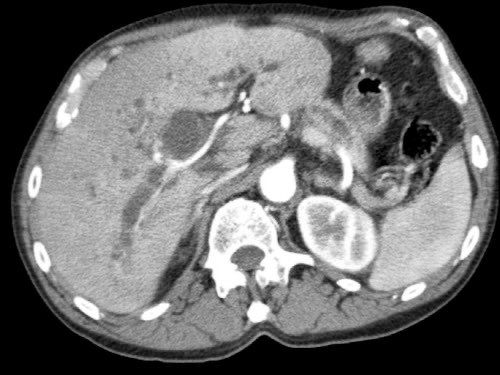

CT axial cho thấy:

- Khối u ở thân tụy (đầu mũi tên trắng).

- Tiếp xúc khu trú < 90º với động mạch mạc treo tràng trên (SMA).

- Tiếp xúc rộng hơn từ 90º – 180º với SMV, SMV bị hẹp nhẹ và biến dạng (mũi tên vàng).

- Giãn ống tụy